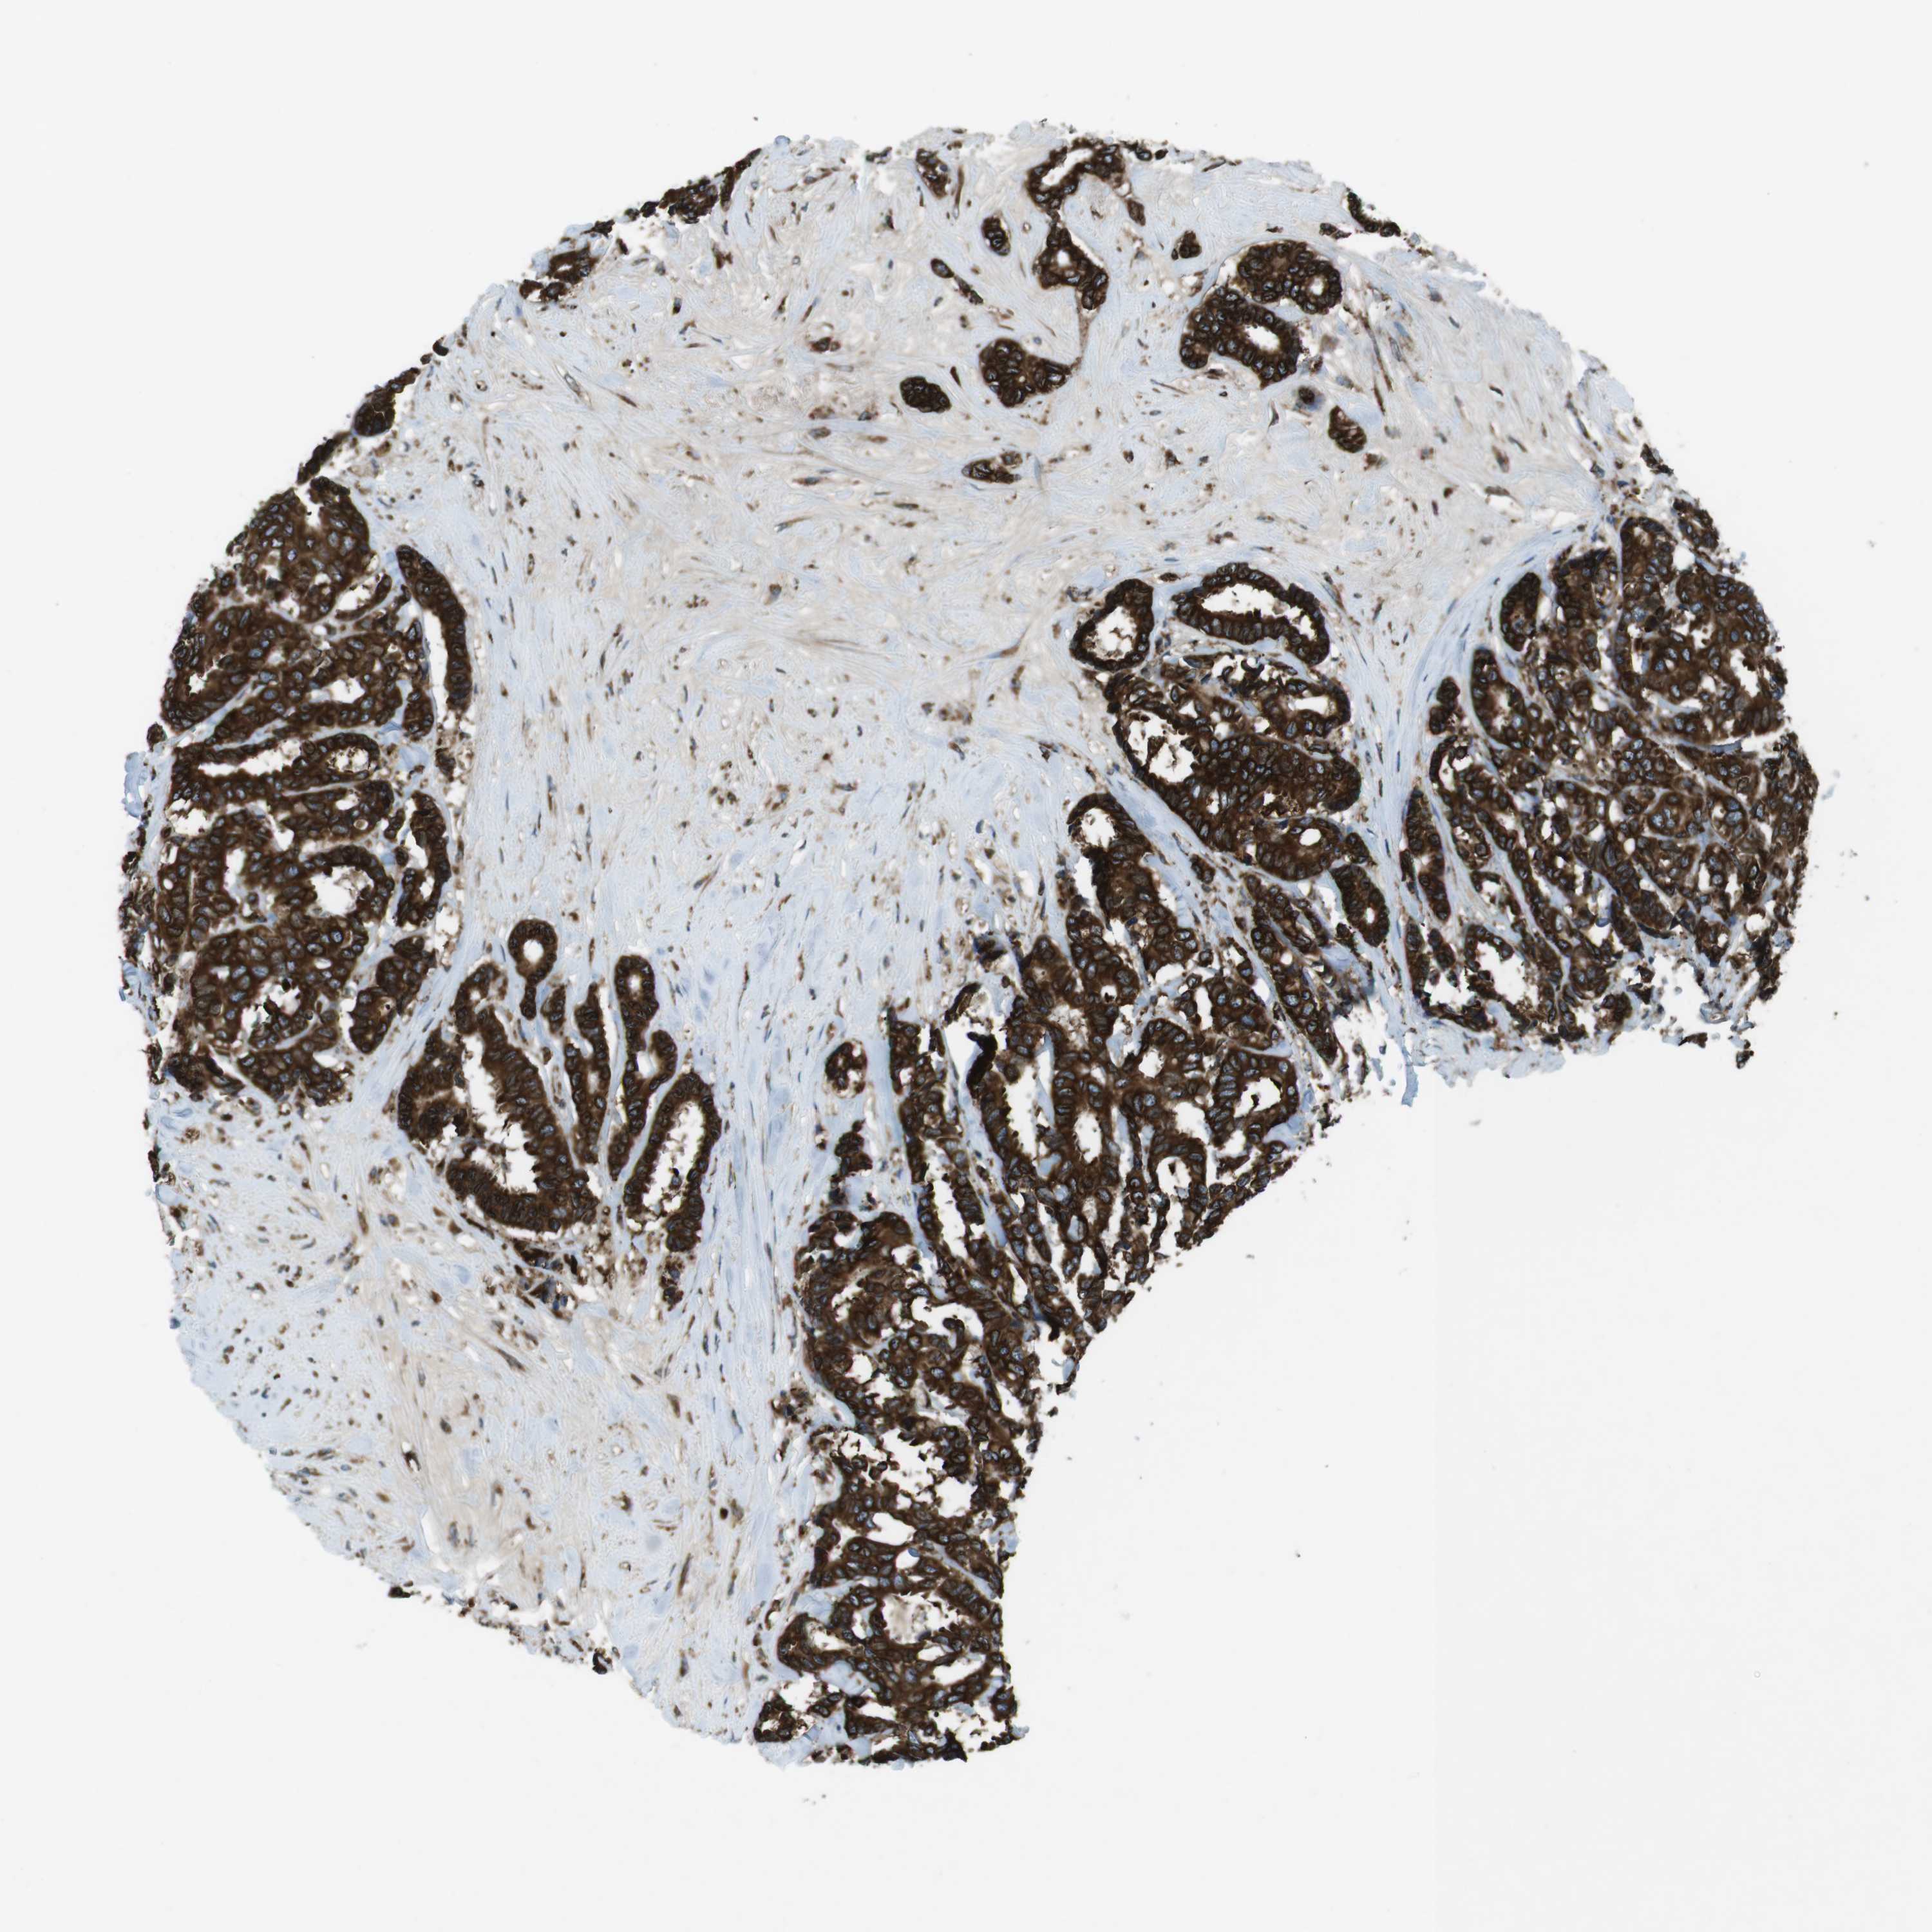

CANCER BREAST CANCER Show tissue menu

BRCA TCGA BRCA VALIDATION PROTEIN EXPRESSION